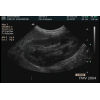

Vessie

Durée. 3:33                 Dr Guy Beauregard